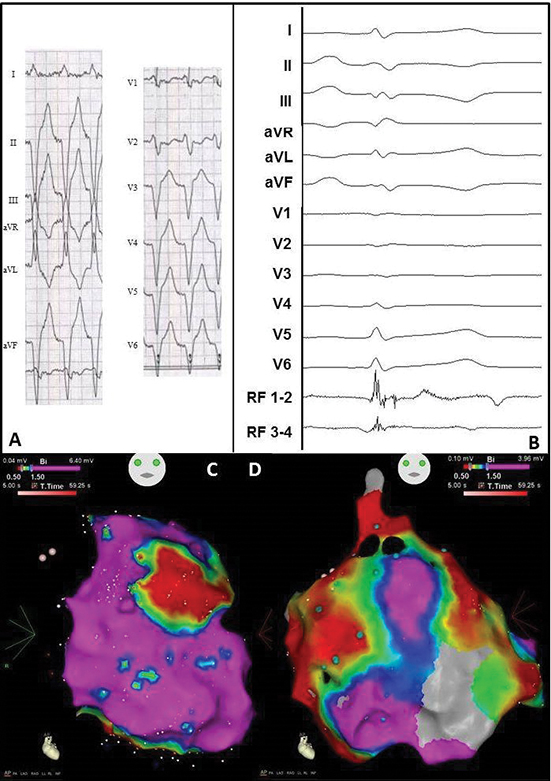

One month later a hybrid VT ablation was performed for recurrences despite the use of amiodarone and metoprolol ([Figure 4A]). Endocardially, the exit site of the clinical VT was mapped at area 8 (inferoposterolateral). A second VT with a more septal exit could be induced as well. The exit zones and late potentials [Figure 4B] were ablated (14 applications, mean 70 seconds, average output 39W). Adhesions and grafts of the previous cardiac operation, hindered the procedure, but safe mapping and ablation could be performed. The epicardial voltage map correlated with the endocardial map [Figure 4C-Figure 4D]. The exit was also mapped at area 8 (inferoposterolateral), and this zone and late potentials were ablated epicardially (11 applications, mean 45 seconds, average output 34W). Because of transient ST-segment elevations inferior, no more VT induction or ablation was performed. After 2 days in the intensive care unit, and 2 days on the regular ward, the patient was discharged.

Figure 4 Electrocardiogram and electro-anatomical maps of case 2

A. Twelve-lead electrocardiogram showing a ventricular tachycardia (150bpm) with right bundle branch block morphology, right axis and normal R-wave transition suggesting a lateral-basal origin in the left ventricle.

Pseudo delta wave and wide QRS suggest epicardial origin.

B. Recording obtained in sinus rhythm during the procedure showing local abnormal ventricular activation. RVAD/P = right ventricular apex distal/proximal, RF = radiofrequency.

C. Inferior view of the bipolar endocardial voltage map showing low voltages inferior/inferoposterior (area 5/6). Red dots = RF applications, purple dots = late potentials.

D. RAO view of the bipolar epicardial voltage map showing low voltage area practically consistent with the endocardial map, though more extensive at the lateral wall (area 7/8). Red dots = RF applications, purple dots = late potentials.